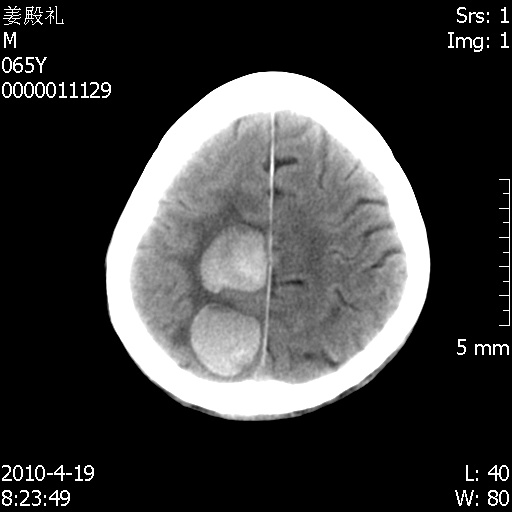

向大家通报一下影像复查结果:

今天上班后发现病人前天复查(4月18日发病,19日初诊,22日复查),三个病灶均明显增大,边缘仍旧清楚,水肿加重,右侧脑室基本闭塞。

基于这样的表现,不知大家有什么看法?(临床其他检查我还没有追踪)

我想:如果是肿瘤出血的话,一般不会导致体积明显改变,水肿又进一步加重;如果是出血灶,那么现在应该正好是水肿加重的时候,还是比较符合,但是为什么边缘又是这样的特点?